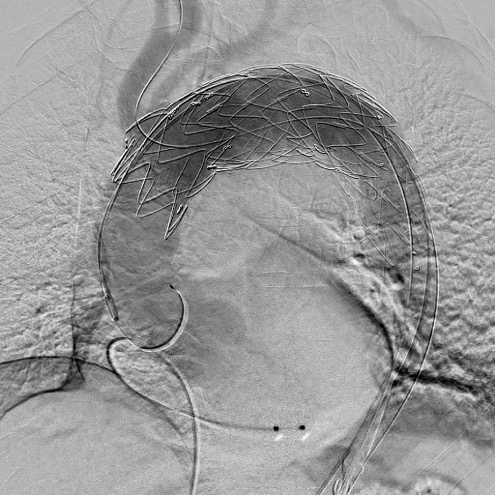

ステントグラフト挿入後